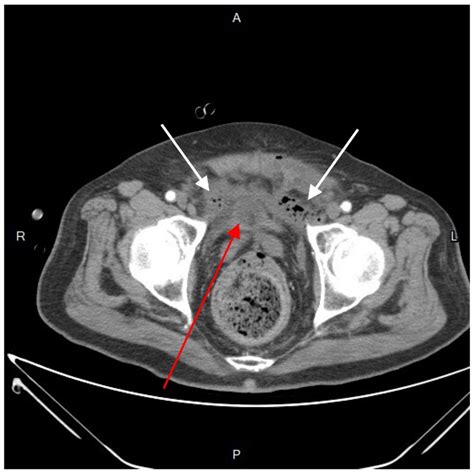

Diagnosing a perianal abscess typically involves a physical examination by a healthcare provider. The doctor will examine the affected area and may ask about symptoms and medical history. In some cases, additional tests may be necessary to confirm the diagnosis or rule out other conditions. These tests may include:

• Imaging Tests: Such as an ultrasound or CT scan to visualize the abscess and surrounding tissues.

Perianal Abscesses Pictures

Visual aids can be incredibly helpful in understanding medical conditions. While it’s important to note that viewing perianal abscesses pictures can be graphic and may not be suitable for all audiences, they can provide a clear understanding of what these abscesses look like. These images often show the redness, swelling, and drainage associated with the condition. If you are considering viewing such images, it is advisable to do so under the guidance of a healthcare professional.